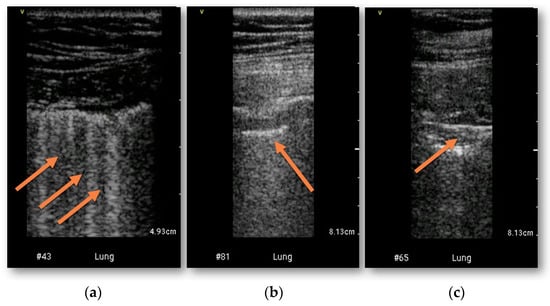

Lung lesions typical for COVID-19 were confirmed in CT in 53 (84%) patients (Figure 1). Ground glass opacities were present in 50 patients, pleural thickening in 21 patients and subpleural consolidation in 28 patients. Lung abnormalities were detected in HUD examination in 50 patients (>3 B-lines in 43 patients, thickened pleural line in 25 patients and subpleural consolidation in 25 patients) (Figure 1). The sensitivity and specificity of bedside HUD examination for diagnosing lung involvement was 92% and 90% retrospectively, AUC = 0.92, p < 0.0001. Weighted Cohen’s kappa was 0.735 (± 0.111, 95% CI 0.517–0.953). The highest concordance with CT was found for pleural thickening (kappa 0.788 ± 0.07, 95% CI 0.651–0.926). The detailed comparisons of bedside HUD examination and CT for diagnosing lung involvement are presented in Table 2.

Figure 1.

Examples of lung ultrasonography performed with HUD. (a) increased number of B-lines; (b) pleural thickening; (c) subpleural consolidation (abnormalities marked with arrows).